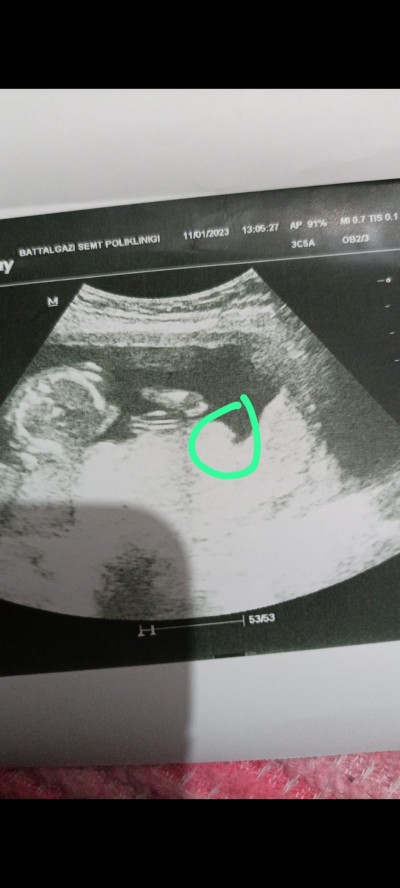

Sizce de o görünen pipi mı yoksa kordon olabilr mi ya çok merak ediyorum doktor da emin konuşmadı sadece benziyor dedi